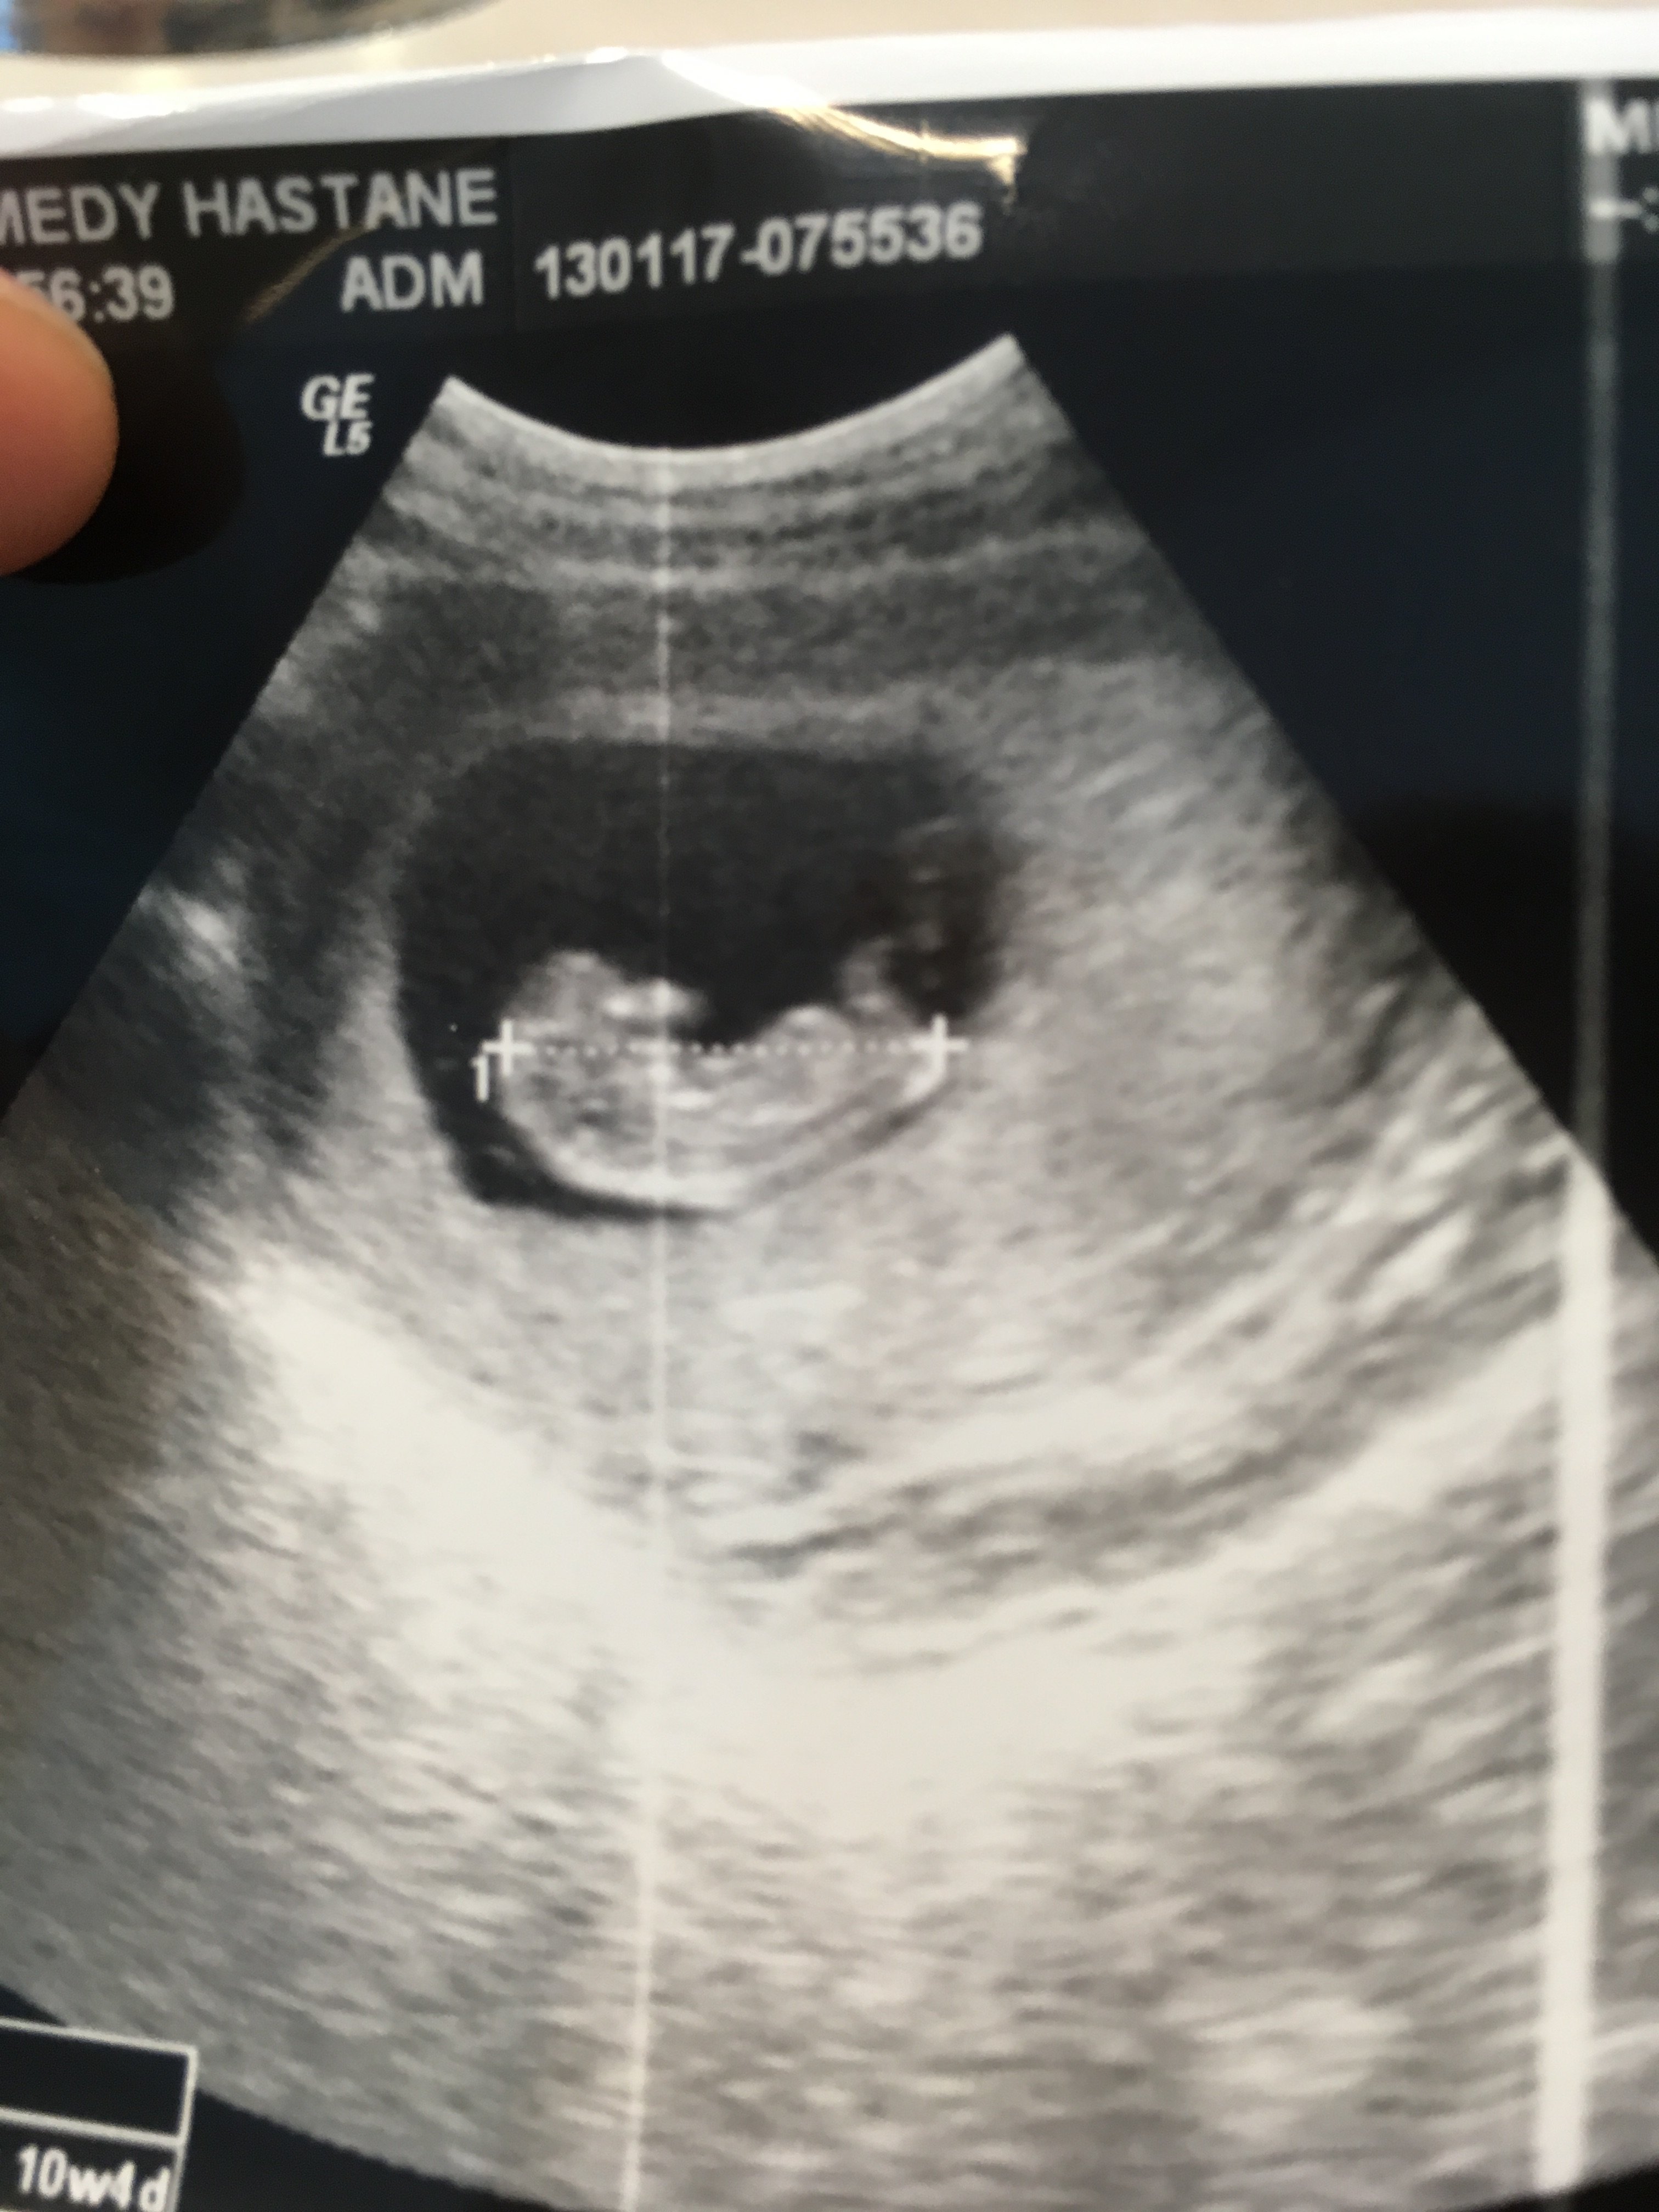

B Burcubayburtlu Yeni Üye Üye 21 Ocak 2017 #148 Merhaba 11 haftalik hamileyim bebeğimin cinsiyetini öğrenebilir miyim? Ekli dosyalar IMG_1090.JPG 1,1 MB · Görüntüleme: 621